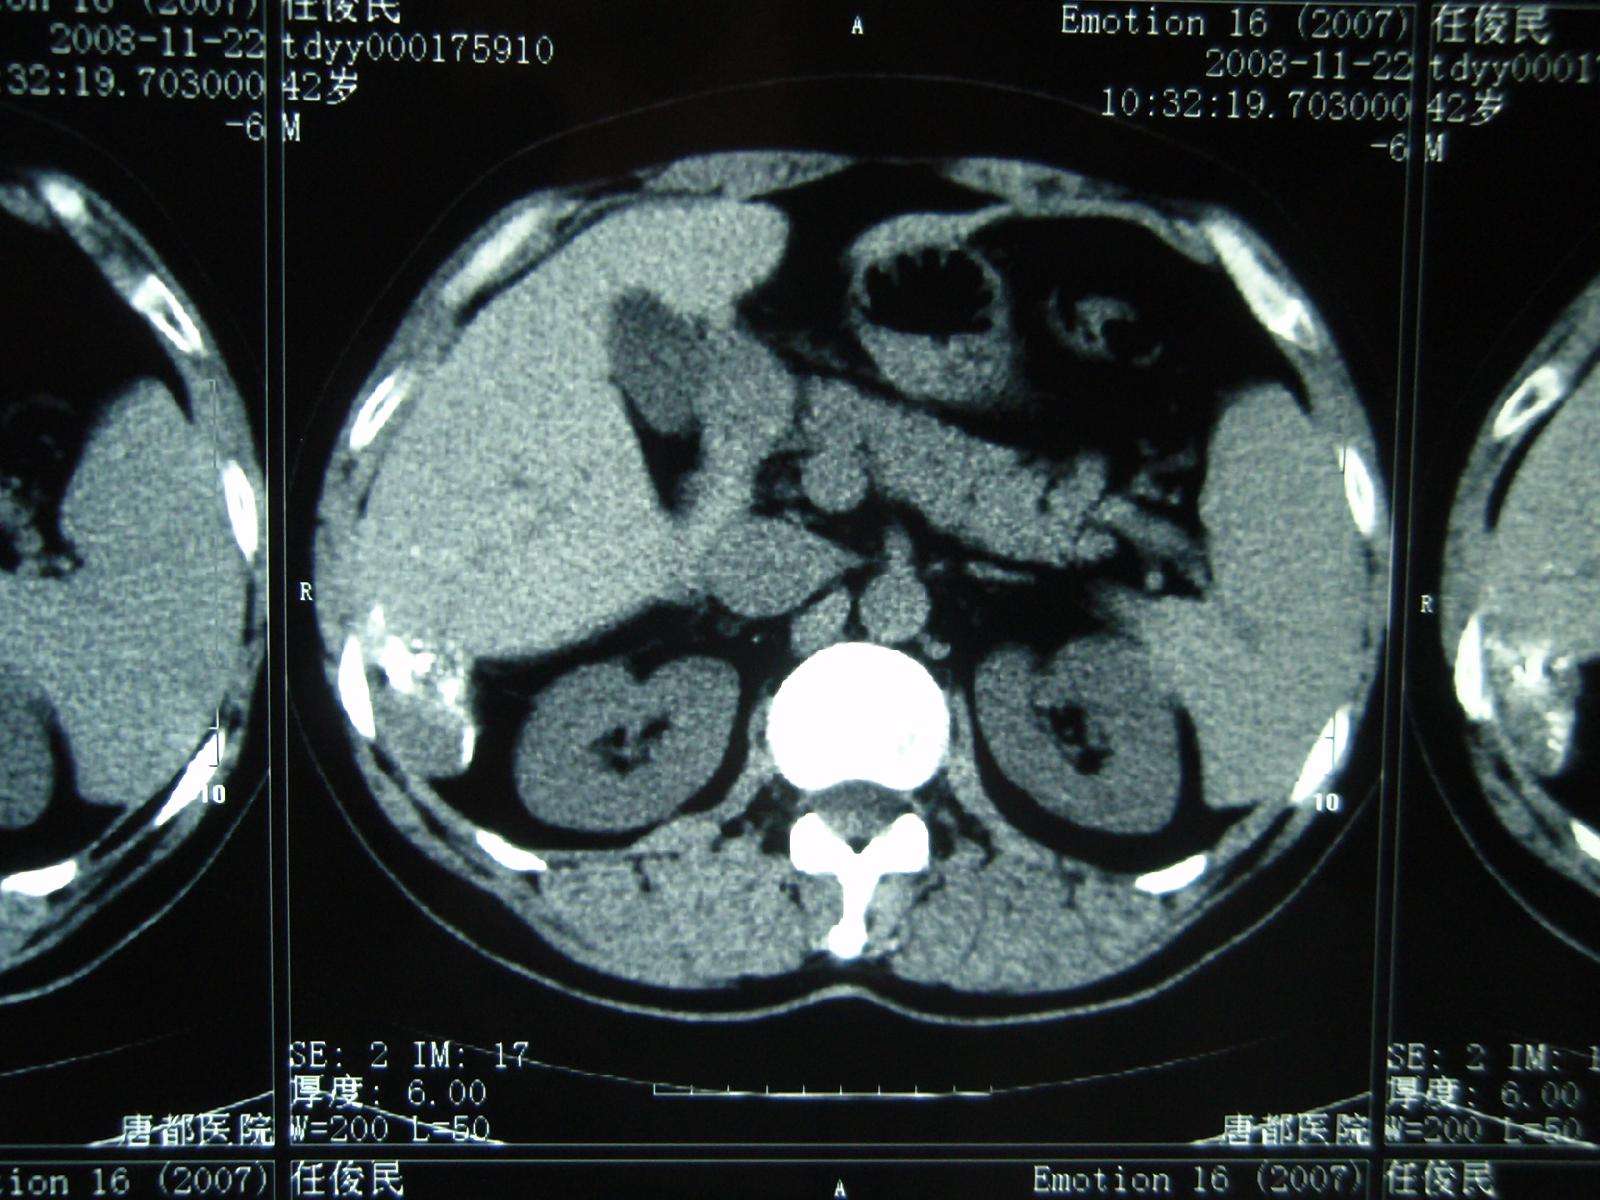

2008年11月22日,栓塞后8个月复查CT显示病灶进一步缩小,仅留一些碘化油沉积,相当于原来的几分之一,病灶完全治愈!